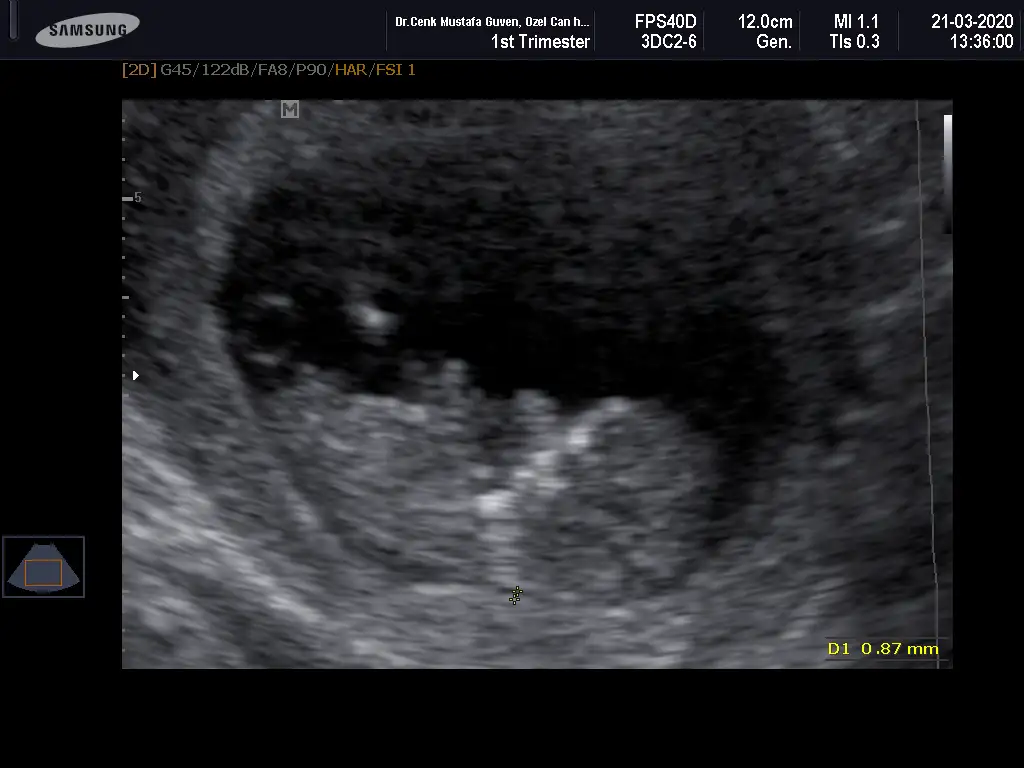

Bir de bunu verdi doktor. Sanırım bacak arası ve kenardakiler de bacakları burada. 11+6 idim.

16,3 KB · Görüntüleme: 65